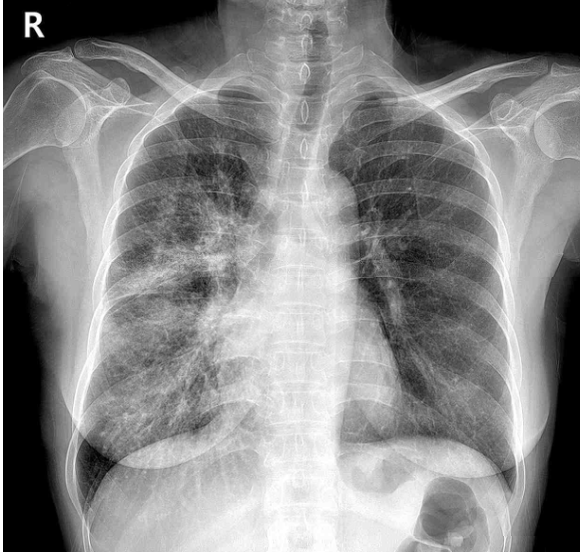

63세 여자가 2주 전부터 가래에 피가 묻어 나와서 병원에 왔다. 평소 계단을 오르면 숨이 찬다고 한다. 비흡연자이다. 혈압 110/70 mmHg, 맥박 80/분, 호흡 15회/분, 체온 36.5°C이다. 오른쪽 가슴에서 호흡음이 감소되어 들린다. 가슴 X선 사진과 가슴 컴퓨터단층촬영 사진이다. 혈액 검사 결과는 다음과 같다. 검사는?

CXR, CT: Irregular marginated mass involving RLL bronchus

• CXR 및 chest CT상 RLL bronchus를 침범하는 불규칙한 경계의 종괴가 관찰되며, 이는 폐암을 강하게 의심할 수 있는 소견이다.